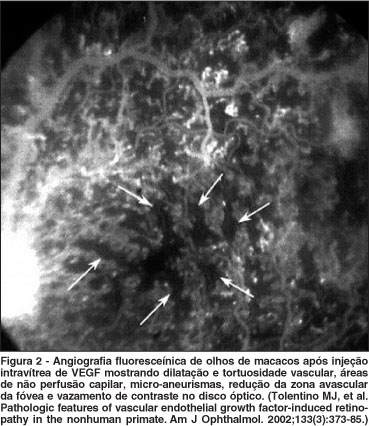

Os estudos em animais mostram que a expressão aumentada de VEGF é uma condição necessária para a indução da neovascularização ocular, e que somente esse aumento é suficiente para induzir esse processo. O aumento da expressão de VEGF no EPR e nos fotorreceptores de ratos promove aumento da permeabilidade vascular, aumento da adesão leucocitária e formação de neovasos de coróide(35). Em macacos, a injeção intravítrea de VEGF provoca o aparecimento de neovasos retinianos cujas características histológicas e funcionais são muito semelhantes aos encontrados nas retinopatias proliferativas(42-43) (Figura 2). Por outro lado, a injeção intravítrea de anticorpo anti-VEGF previne a formação de neovasos sub-retinianos(23) (Figura 3).

42. Tolentino MJ, Miller JW, Gragoudas ES, Jakobiec FA, Flynn E, Chatzistefanou K, et al. Intravitreous injections of vascular endothelial growth factor produce retinal ischemia and microangiopathy in an adult primate. Ophthalmology. 1996;103(11):1820-8.

43. Tolentino MJ, McLeod DS, Taomoto M, Otsuji T, Adamis AP, Lutty GA. Pathologic features of vascular endothelial growth factor-induced retinopathy in the nonhuman primate. Am J Ophthalmol. 2002;133(3):373-85.